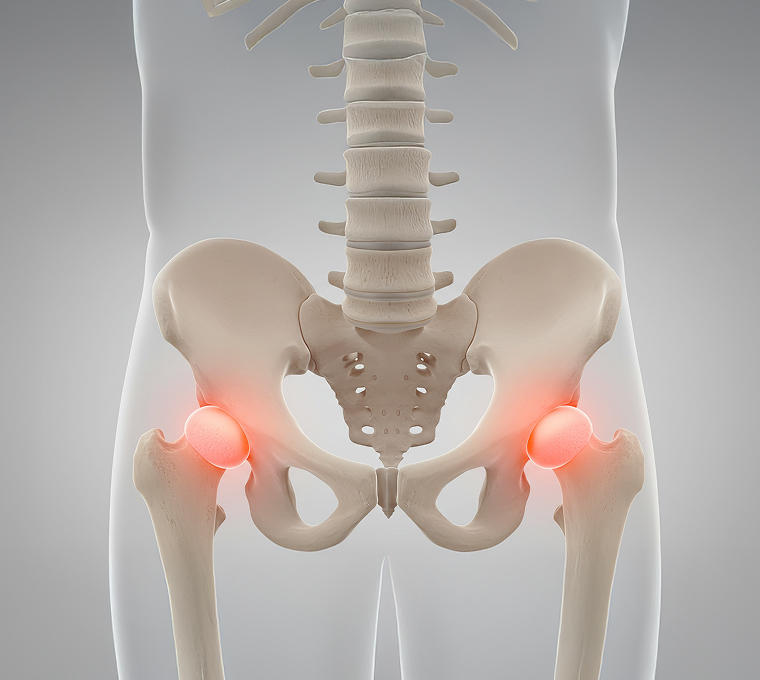

계단 오르기조차 힘든 무릎,

나이 탓만 하지 마세요!

무릎, 관절 손상의 원인을 분석해

연골 보호와 염증 반응을 개선할 수 있습니다.